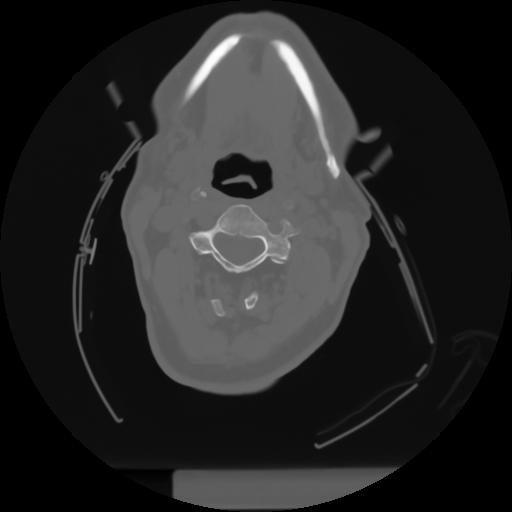

10 P.BLANDAS,,Axial,2.0,P.BLANDAS,,